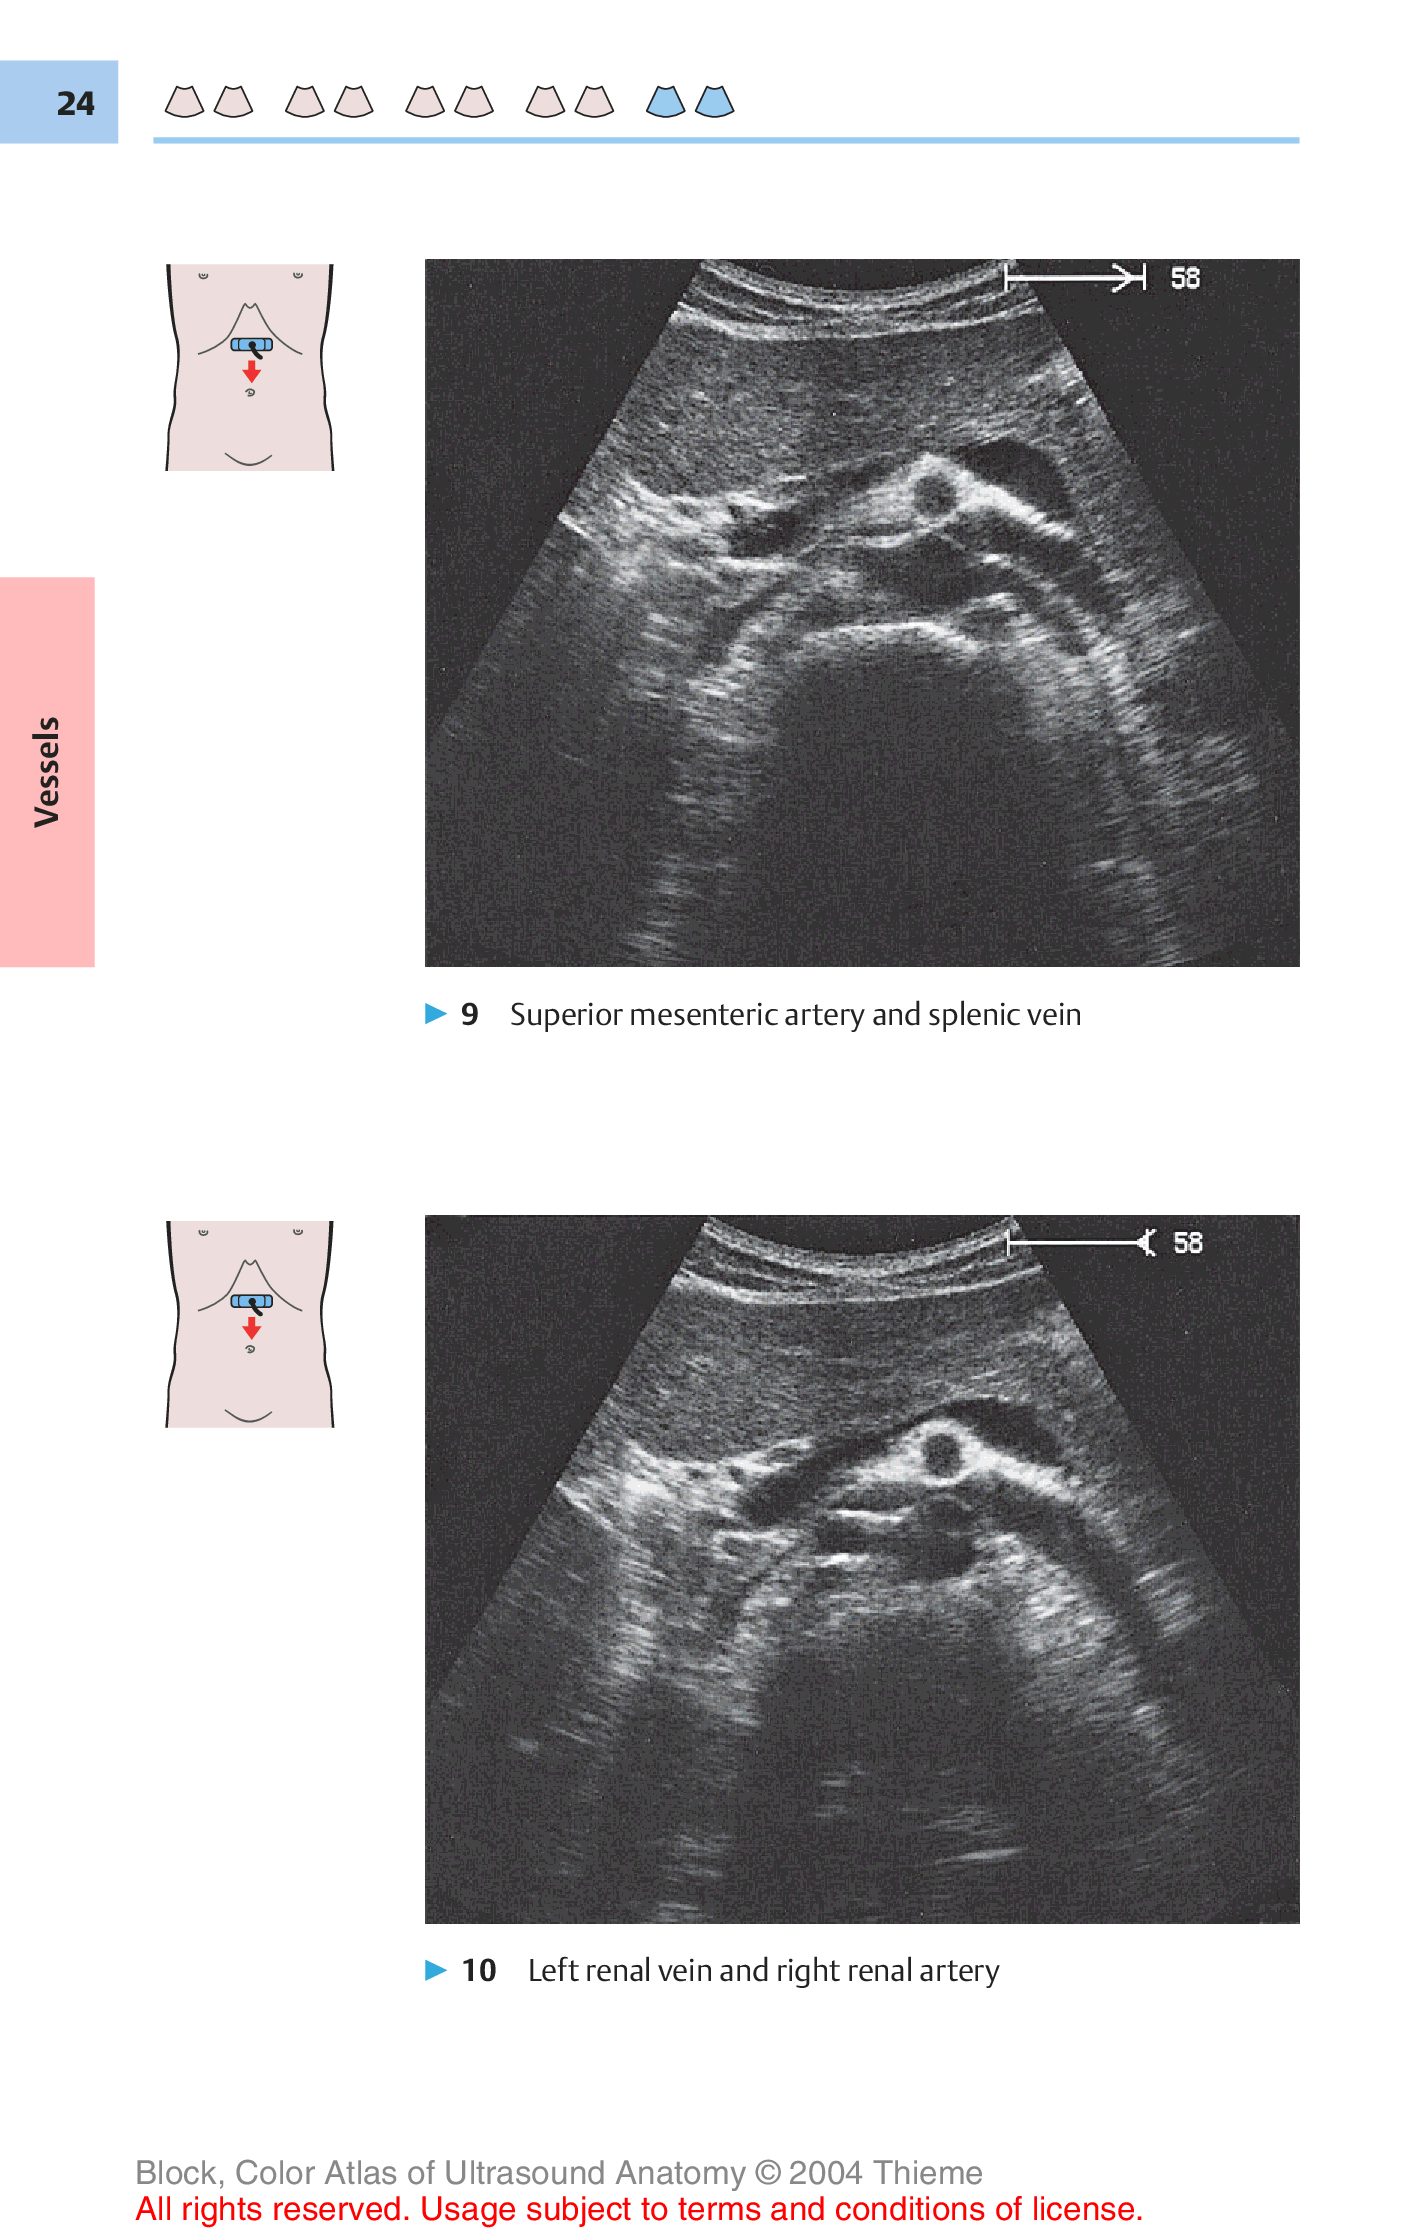

"Color Atlas of Ultrasound Anatomy" - читать интересную книгу автора (Berthold Block)